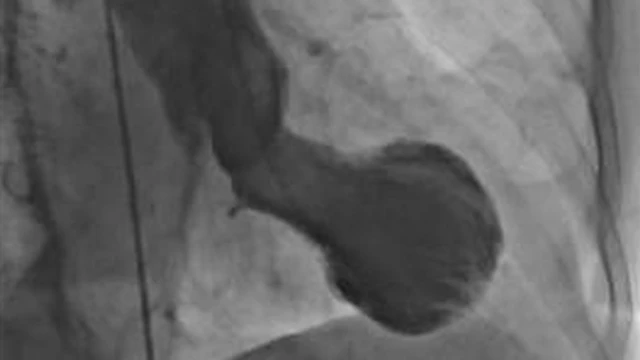

Le syndrome du cœur brisé est également connu sous le nom de "syndrome de takotsubo", en raison de la similitude de la forme du cœur des personnes atteintes de cette affection avec la marmite japonaise du même nom.

Crédit photo, Christian Templin, UNiversidad de Zúrich